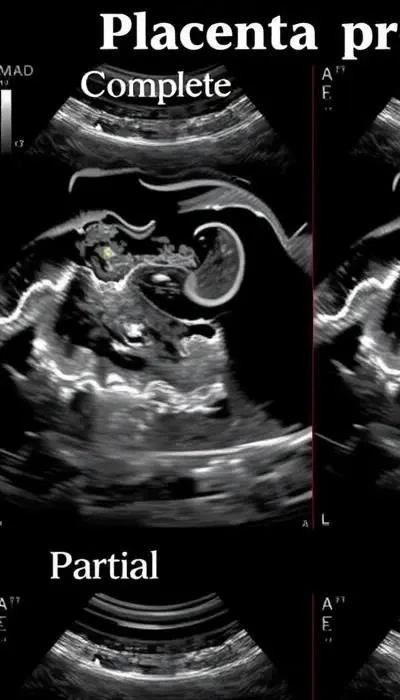

Предлежание плаценты – это состояние, при котором плацента располагается в нижней части матки, частично или полностью закрывая внутренний зев шейки матки. Это может привести к кровотечениям во время беременности, особенно в третьем триместре, и требует тщательного наблюдения и ведения беременности. В 2026 году, благодаря современным методам диагностики и лечения, риски для матери и ребенка значительно снижены, однако важно своевременно выявлять и правильно тактически вести беременность при данном диагнозе.

Спектр приращения плаценты включает различные степени врастания плаценты в стенку матки, что увеличивает риск кровотечения во время беременности и родов. Диагностика предлежания плаценты в основном проводится с помощью ультразвукового исследования (УЗИ), которое позволяет определить положение плаценты и исключить другие патологии.